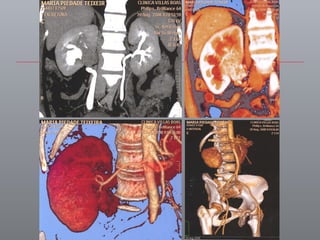

AVANÇOS DE IMAGENS / ONCOLOGIA PESQUISANDO O TUMOR Limites estratégicos / precisão cirúrgica IRCAD

NAVEGAÇÃO CIRÚRGICA Segurança ou risco na direção do corte Vermelho: arteria renal e aorta   /  azul: veia renal

MAIOR PRECISÃO CIRÚRGICA Sistemas de navegação